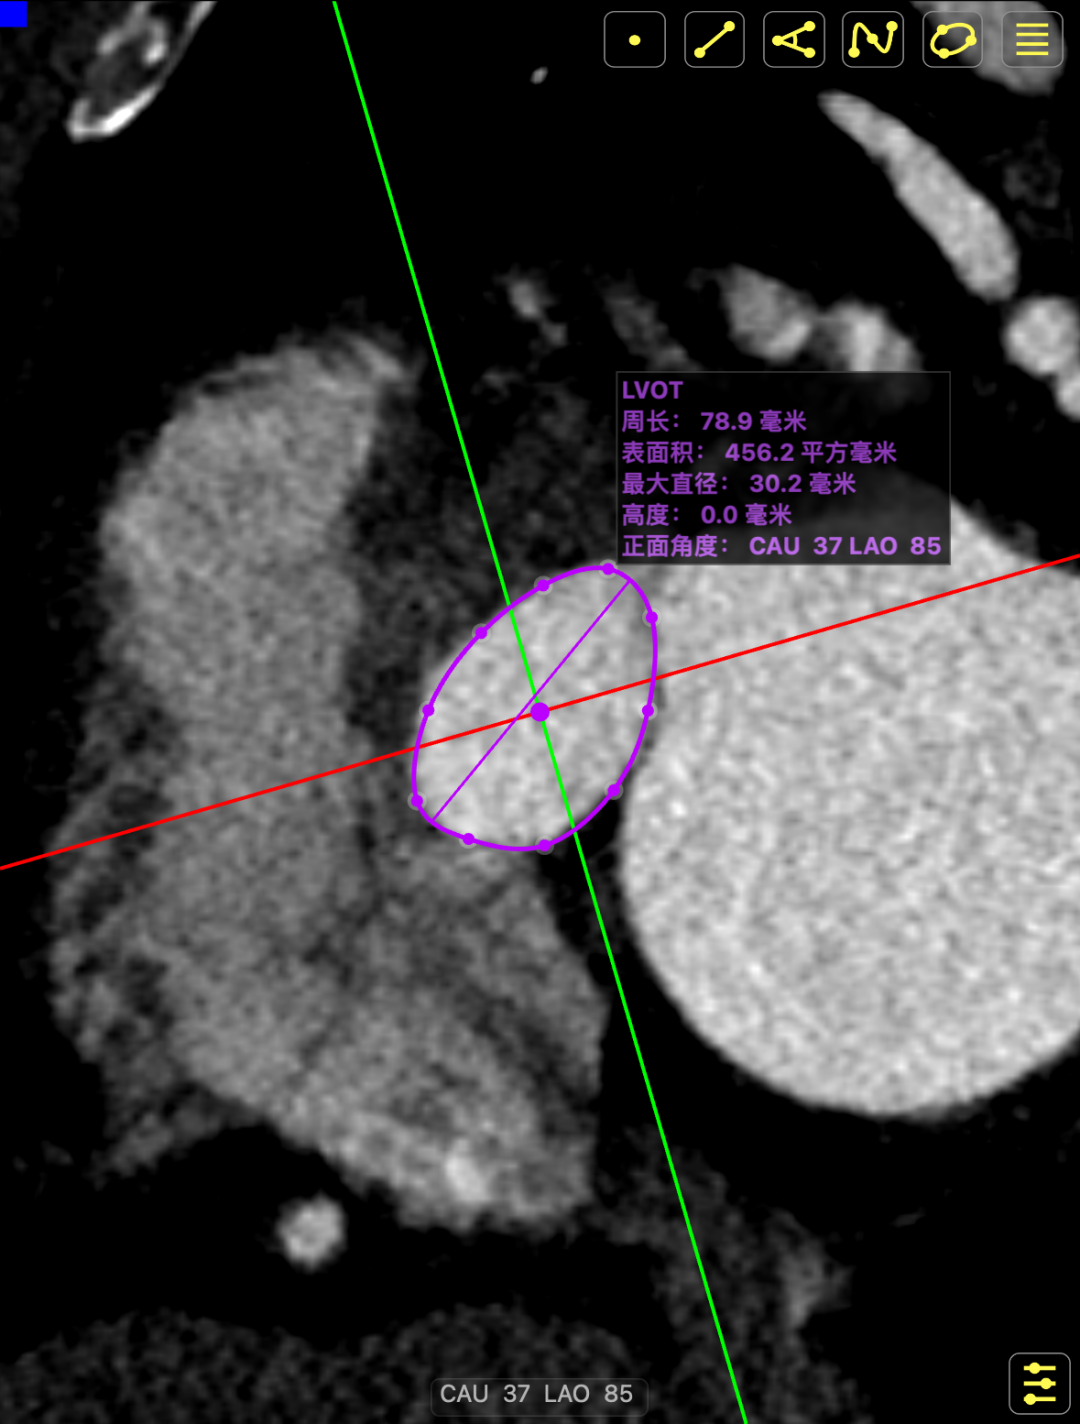

CT影像

CT影像